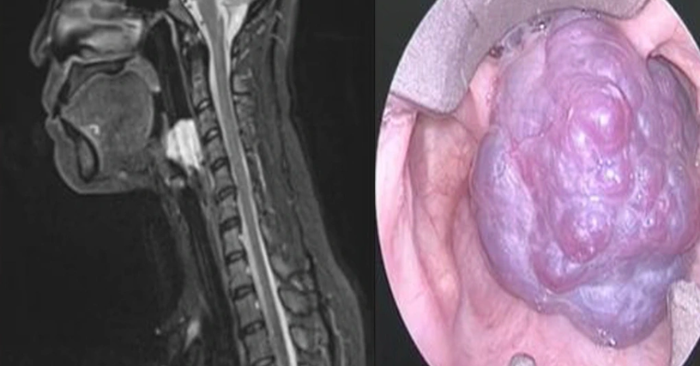

Tại Hội nghị Khoa học Đầu cổ châu Á – Thái Bình Dương (ASHNO 2025) diễn ra ở TP.HCM, bác sĩ Nguyễn Trương Khương, Giám đốc Chuyên môn Bệnh viện Đa khoa Quốc tế Nam Sài Gòn, đã thu hút sự chú ý của hàng trăm chuyên gia quốc tế khi trình bày ca phẫu thuật đặc biệt: u máu chiếm trọn thanh quản – một bệnh lý hiếm gặp đến mức y văn thế giới gần như chưa từng đề cập.

Bệnh nhân là chị A., 40 tuổi, sống tại TP.HCM. Hai tháng trước khi nhập viện, chị thường xuyên cảm thấy vướng họng, nghẹn khi ăn và khó thở. Ban đầu, chị chủ quan nghĩ chỉ là viêm họng hoặc rối loạn tiêu hóa nên tự mua thuốc uống. Khi triệu chứng ngày càng nặng, chị đến bệnh viện kiểm tra và được phát hiện có khối u máu lớn chiếm gần toàn bộ lòng thanh quản.

Sau khi thăm khám kỹ, bác sĩ Khương nhận định đây là ca bệnh cực kỳ hiếm: “Khối u máu phát triển trong lòng thanh quản khiến bệnh nhân khó thở, nói khó, nguy cơ tắc đường thở cấp tính bất cứ lúc nào. Y văn quốc tế cũng rất ít ghi nhận ca tương tự.”